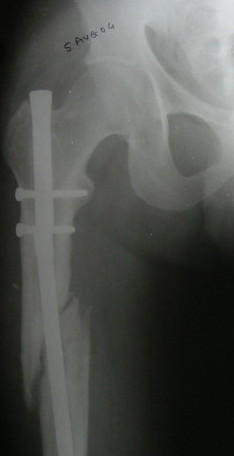

Locked nailing femur

Dear All, Requesting your opinion 21 year old thin built student, sustained long oblique # upper third Rt femur in Sept2003. Locked nailing done (probably open) in Sept 03; two proximal and one distal locking done elesewhere. Wt bearing started 8 weeks later.

Came to me in May 2004 with some pain at the # site. That time though clinically the fracture seemed sticky, the xrays did not show any callus. I had advised exchange nailing with a bigger nail. He went away and got bone grafting done with the implants in situ in June 2004. The weight bearing was started immediately. Check Xray taken in Aug 04 showed the distal screw broken as well as the nail just beyond the 2nd proximal screw. He was advised to continue wt bearing and wait and watch. He once again came to me 3 days ago because of pain at the # site and a feeling of movement at the #site. Clinically the fracture seems united with no pain on movem,ents. The xrays taken now are being enclosed. The AP view shows the # line still visible, though the callus is seen in between and the lateral view shows continuity. The nail break is obvious now. What do we do now? 1) Wait and watch and let the implants remain. 2) Do an exchange nailing with a thicker nail. Kindly note. a) the nail is going towards the medial aspect of the lower end thus causing a 5* varus at the # site. b) there is a slight overiding causing a centimeter of shortening.c) Implant removal may not be easy with the distal screw broken and the nail broken too. Regards V M Iyer . Iyer Orthopaedic Centre, 103,Railway lines Solapur India.413001.